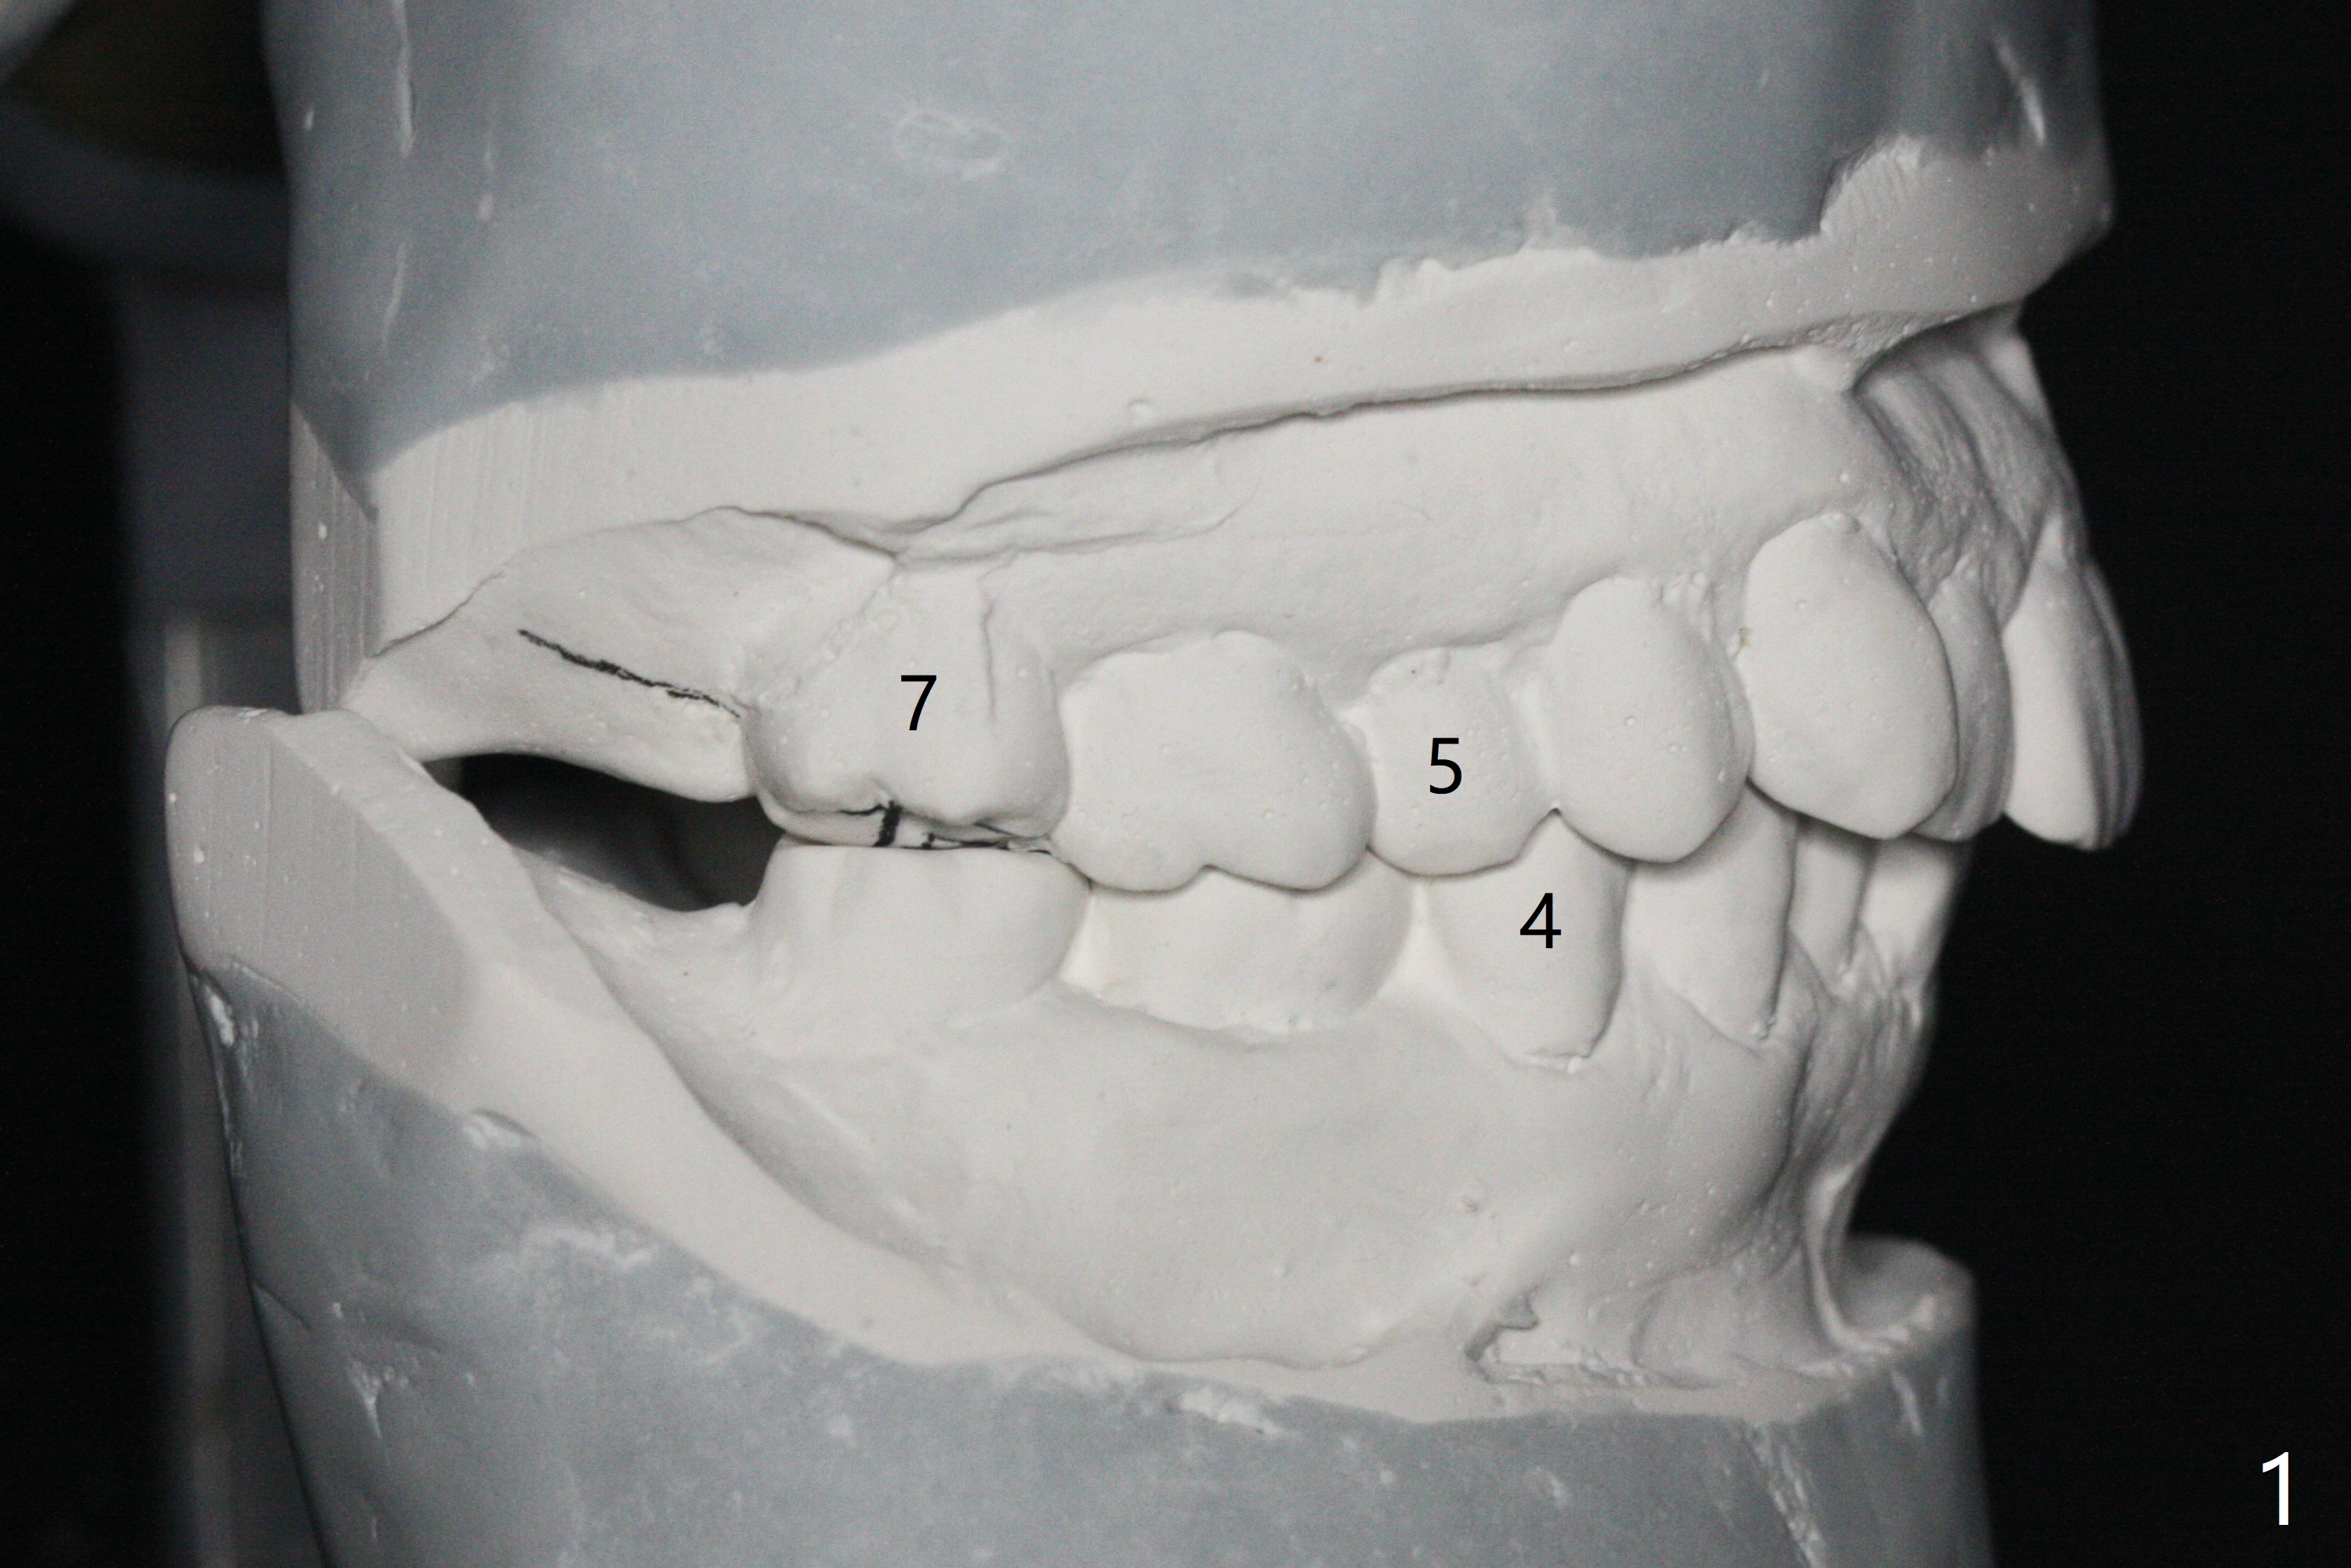

A 54-year-old man remains difficult in mastication in spite of implant placement at #14 and 31 (Fig. A, B, E, including screw loosening (poor trajectory at #14)). In addition to 2 more implants at #15 and 18 with guide, malocclusion seems to be necessary to be addressed (Fig.1-5). It appears that UR, LL4 should be extracted for orthodontic treatment (Fig.6-10). To reduce screw loosening, IS guide will be used to place IBS (5x9mm) and tissue-level (5x11mm) implants at #15 (PRF)and 18, respectively. If the one at #14 or 15 keeps loosening, splint #14 and 15 crowns. In fact the patient agrees with limited ortho (UR7 cross bite).